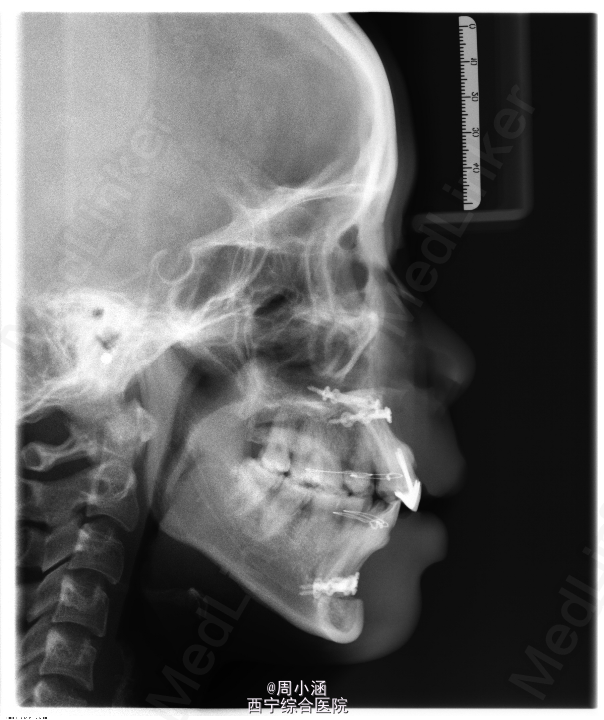

双颌前突,上下颌前牙区根尖下截骨后退术+双侧上颌骨部分切除术+双侧下颌骨去骨皮质术+坚固内固定术+15,24,34,44拔除术

钛板一般在一年后拆除